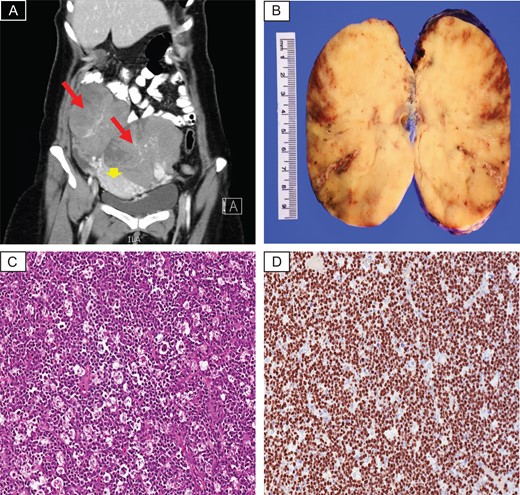

A 42-year-old lady presented to the emergency department at our hospital complaining of continuous abdominal pain and a palpable abdominal mass. No associated symptoms were identified. Physical examination demonstrated tender enlarged abdomen. Her blood work was unremarkable, except for high platelet level (480 × 109/L). Abdominal and pelvic computed tomography (CT) scan with oral and IV contrast revealed large bilateral lobulated soft tissue heterogeneous adnexal masses with some cystic components. There was an evidence of vascular enhancement within both adnexal masses. The largest mass (9.2 × 11.4 cm2). No radiological evidence of cystic rupture or hemorrhage were seen within both masses. The uterus was displaced by both adnexal masses. Both ovaries could not be visualized (Fig. 1A). Bone marrow aspirate showed mild increase in megakaryocytes with no evidence of infiltrative process. Chest x-ray and brain MRI scan were unremarkable for pathologic findings.

(A) CT scan with contrast revealed large bilateral lobulated heterogeneous adnexal masses (red arrows), displacing the uterus down (arrow head). (B) Gross photo showing homogenous white tan cut surface, focal areas of hemorrhage and necrosis are seen. (C) Histopathology examination demonstrates sheets of diffuse lymphoid infiltrate with prominent starry-sky appearance (H&E; ×20). (D) Ki67 proliferative index is almost 100% (×20).

The patient underwent total abdominal hysterectomy with bilateral salpingo-oophorectomy. The specimen sent for pathologic evaluation. We received two separate adnexal masses, the right adnexal tissue composed of a single solid capsulated mass with smooth tan lobulated cut surface weighing 564 g and measuring 12 × 10 × 6 cm3. The left adnexal tissue composed of a single solid mass weighing 1040 g and measuring 15 × 10 × 7 cm3, with homogenous white tan lobulated cut surface, focal areas of hemorrhage and necrosis were seen (Fig. 1B). Microscopic examination of the sections taken from both masses revealed sheets of diffuse lymphoid infiltrate composed of medium sized lymphoid cells with minimal amphophilic cytoplasm, prominent basophilic nucleoli, coarse chromatin and thick nuclear membrane. Prominent starry sky pattern with numerous mitosis and apoptosis seen (Fig. 1C). By immunohistochemistry, the tumor cells revealed positive immunoreactivity against CD79a, CD20, PAX-5, CD10, BCL6 while negative for BCL2, CD3, CD5, CD21, CD23, CD1a, TdT and Cyclin D1. Ki67 proliferative index of 100% expressed in the tumor cells (Fig. 1D). Flow study result showed small lymphoid population expressing CD19, CD20, CD22 and CD10. In the meantime, FISH interpretation revealed positive BCL6 rearrangement and c-MYC (8q24) rearrangement. IGH/BCL2 [t (14; 18)] rearrangement was not detected. All of the above ancillary studies were consistent with the diagnosis BL. The patient planned to be treated with multi-agent chemotherapy R-CODOX and R-IVAC chemotherapy. Our patient currently is on her third cycle, doing well and alive.